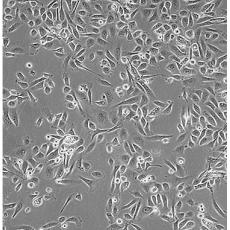

PC-3(PC 3)

產品名稱 PC-3(PC 3)

中文名稱 人前列腺癌細胞

組織來源 前列腺癌;骨髓轉移;男性

細胞種屬 Homo sapiens, human

生長特性 adherent

培養基 Ham's F-12K+10% FBS+1% P/S

形態特征 epithelial

傳代方法 1:3-1:6

培養條件 Atmosphere: Air, 95%; CO2, 5%。Temperature: 37℃

細胞描述 PC-3源于一位62歲白人男性IV級前列腺腺癌患者的骨轉移灶;有低水平的酸性磷酸酶活性和5-α-睪酮還原酶活性。